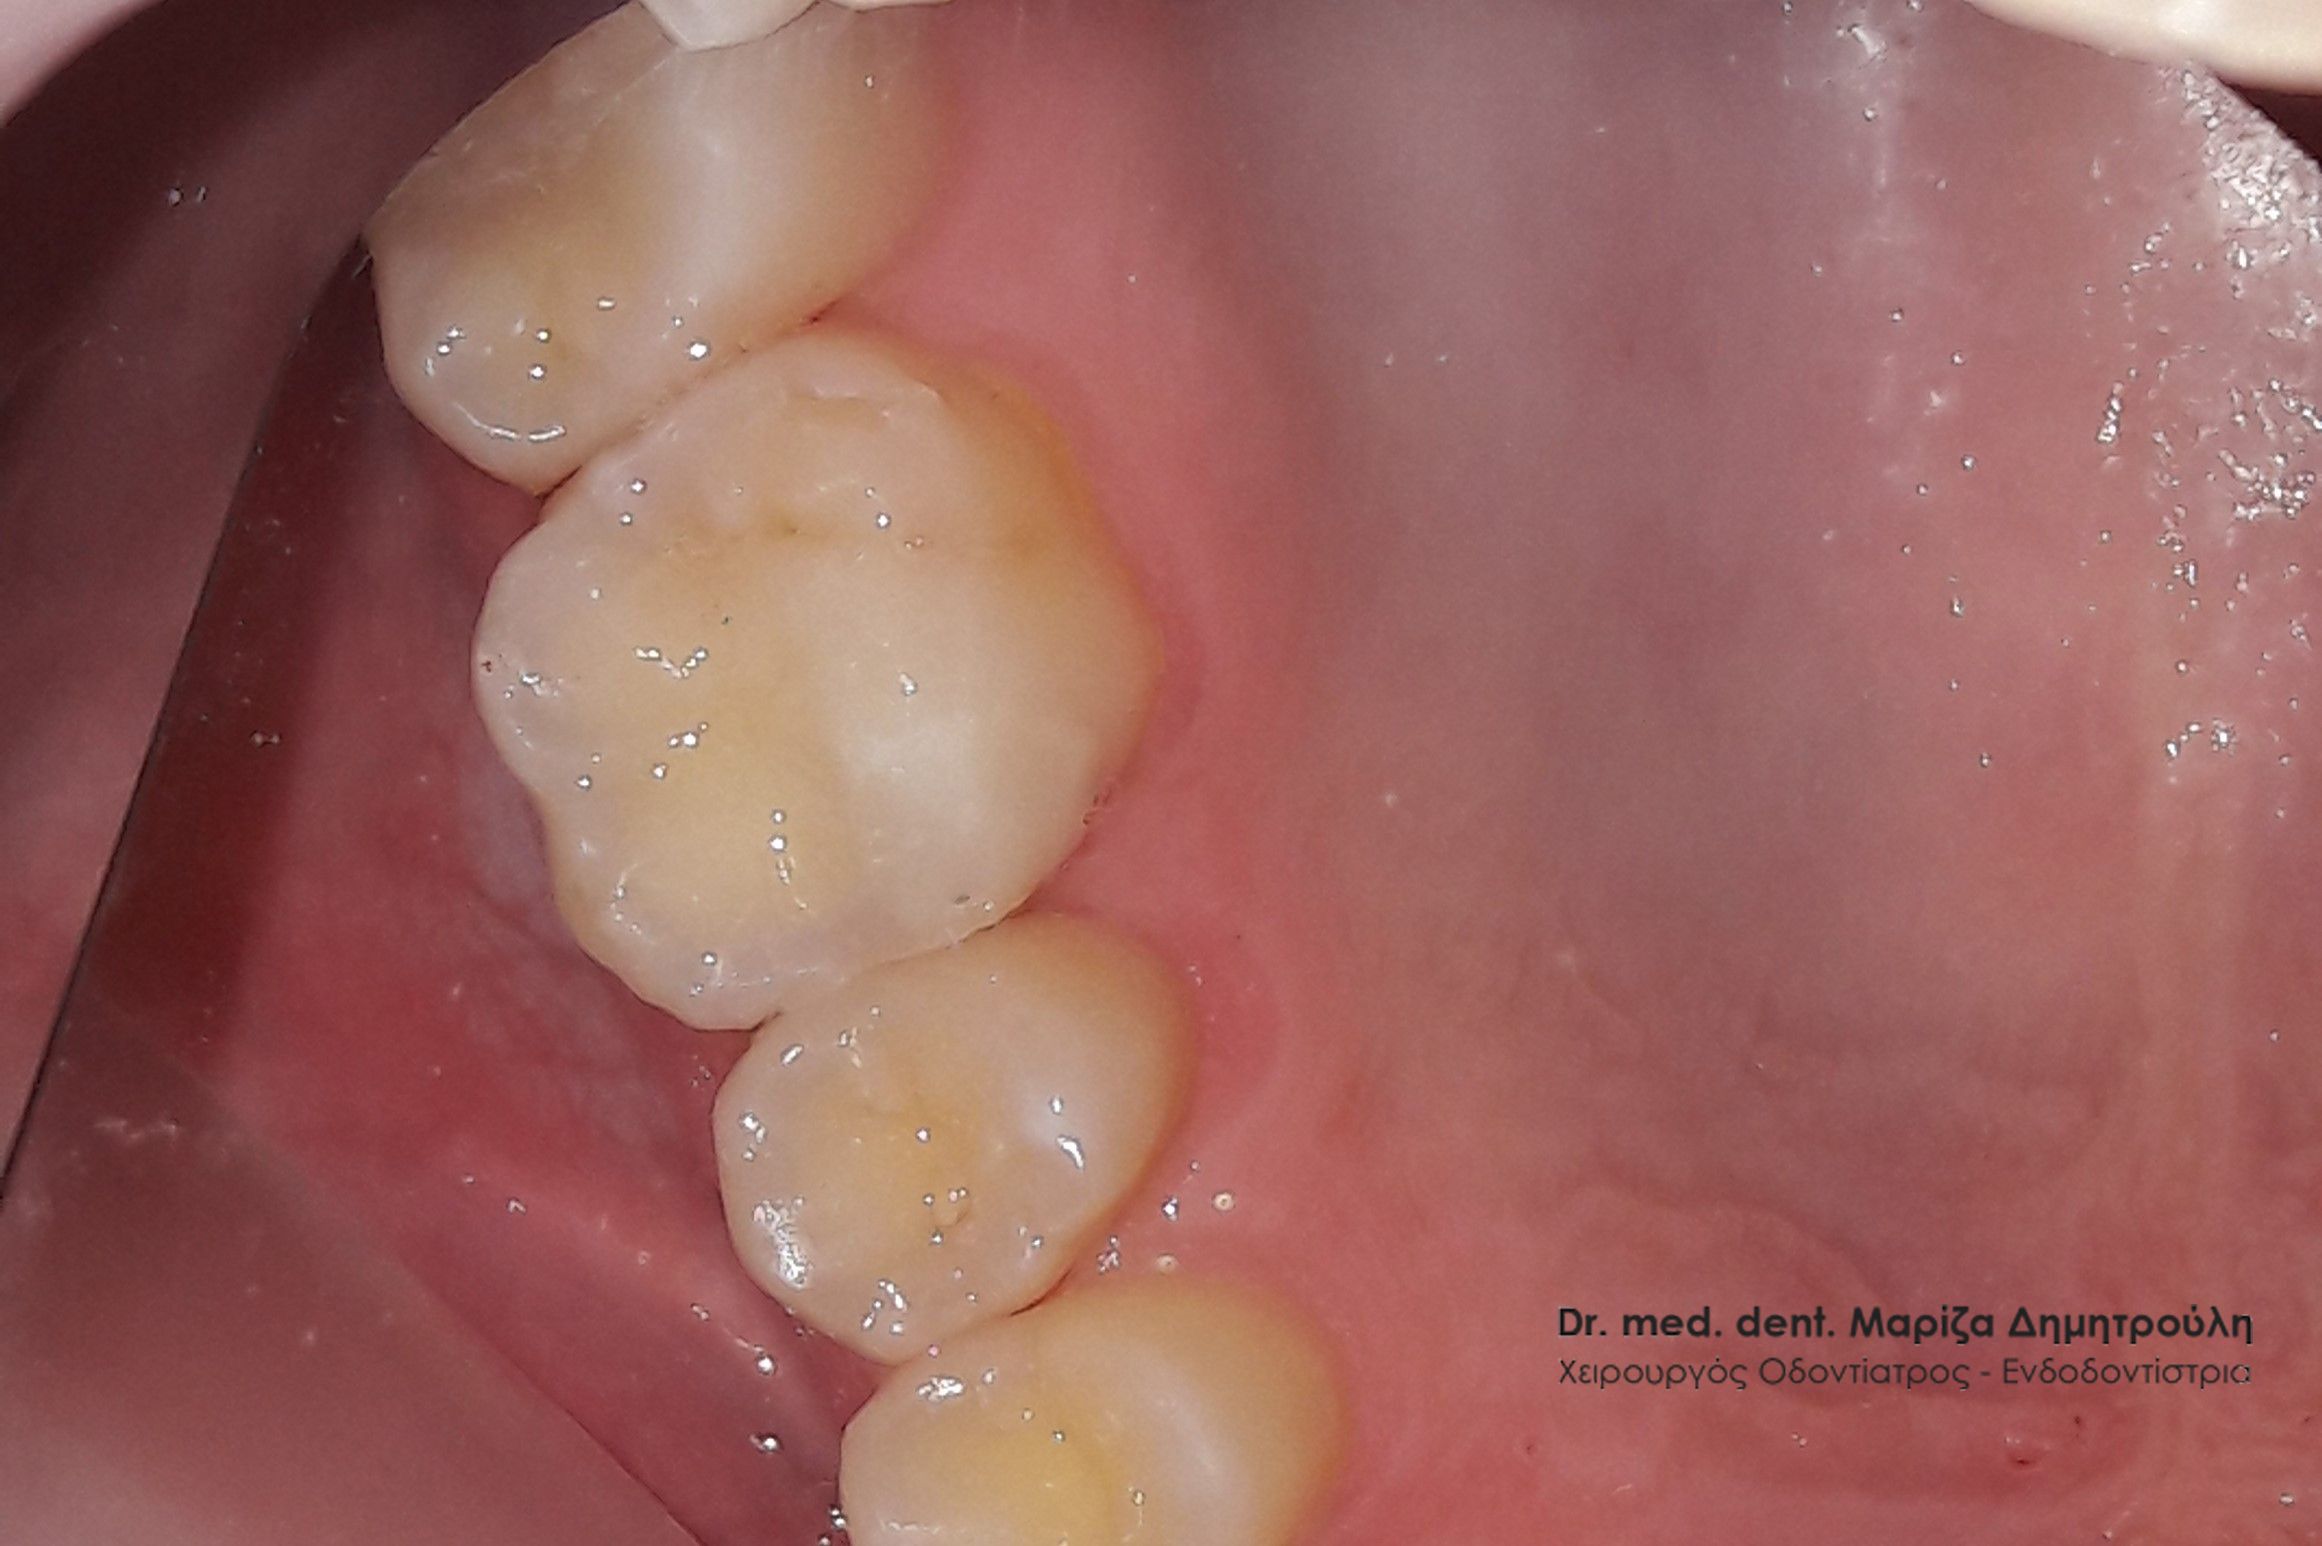

Περιστατικό – Λευκά σφραγίσματα δύο δοντιών

Στο παρόν περιστατικό απουσιάζει η αρχική εικόνα των δύο δοντιών πριν αρχίσει ο εκτροχισμός τους. Διαθέσιμες είναι μόνο η ενδιάμεση εικόνα που παρουσιάζει το εύρος του οδοντικού ελλείμματος στα δύο γομφίους της αριστερής πλευράς της άνω γνάθου και η τελική εικόνα αποκατάστασης των δύο δοντιών.

Η ασθενής αισθανόταν τις τελευταίες μέρες έναν ήπιο πόνο κατά τη μάσηση τροφών. Μετά την κλινική εξέταση του στόματος διαπιστώθηκε η ύπαρξη τερηδονικών κοιλοτήτων στους δύο άνω αριστερούς γομφίους. Αποφασίστηκε με τη συναίνεση της ασθενούς η αντικατάσταση των σφραγισμάτων. Στον πρώτο γομφίο διορθώθηκε μόνο η μισή έκταση του παλιού σφραγίσματος, καθώς κρίθηκε οτι δεν ήταν απαραίτητη η αφαίρεση ολόκληρου του παλιού σφραγίσματος.

ΠΡΙΝ

META